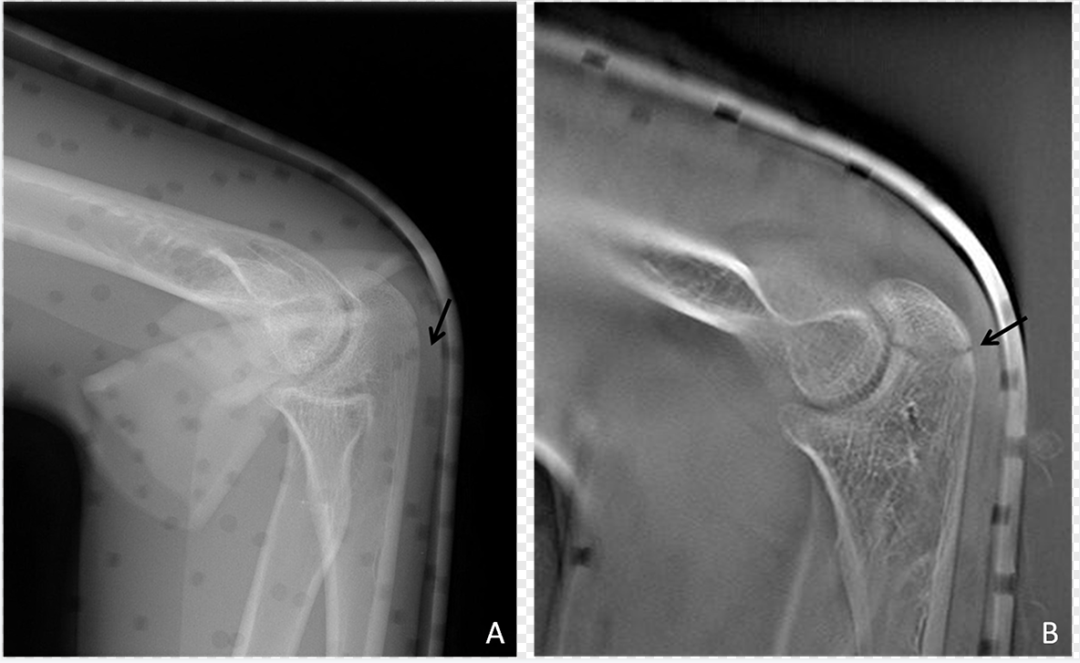

图2  齿状突骨折常规DR与DTS

A.常规DR齿状突及周围组织显示较模糊;B.DTS显示清晰的齿状突骨折线(黑箭)